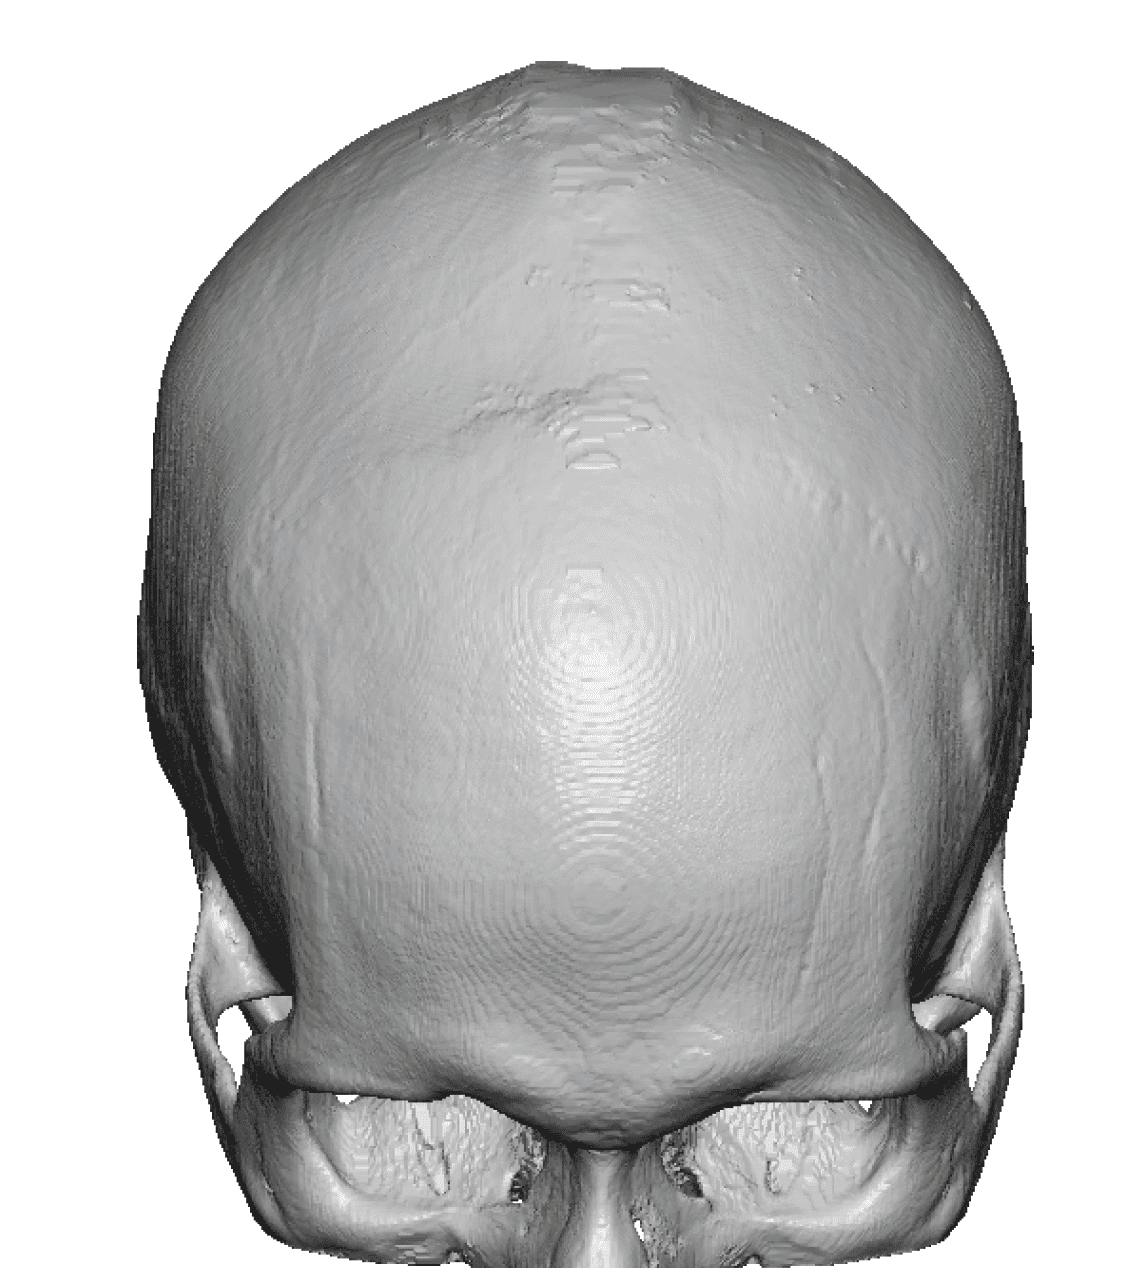

Patient 100

Desire for reshaping of an asymmetric flat back of the head in a shaved head male.

A combined back of the head reshaping procedure was done with a custom skull implant, sagittal ridge reduction and a right temporal muscle reduction.

Desire for reshaping of an asymmetric flat back of the head in a shaved head male.

A combined back of the head reshaping procedure was done with a custom skull implant, sagittal ridge reduction and a right temporal muscle reduction.